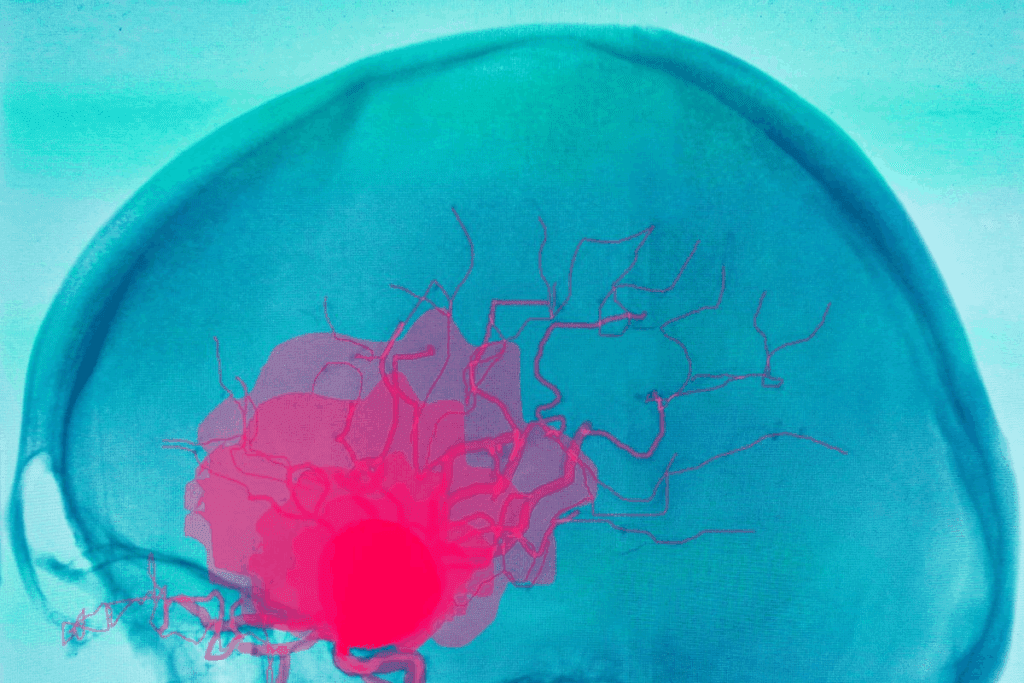

A brain aneurysm is a bulge in a blood vessel in the brain. It can be very dangerous if it bursts, causing bleeding. We at Liv Hospital use a special procedure called brain embolization to treat it. This method stops the aneurysm from bursting by cutting it off from blood flow.

Our team is skilled in using advanced techniques. We can successfully treat over 90% of brain aneurysms. This is a better option for many because it has a shorter recovery time and fewer risks than open surgery.

Embolisation of an aneurysm is a safe way to stop it from bursting. It works by cutting off the aneurysm from the blood flow. This is very important for people with brain aneurysms because it lowers the chance of bleeding and serious problems.

How Embolisation Prevents Rupture

Embolisation stops an aneurysm from bursting by filling it with coils or liquid. This blocks blood from getting in. It keeps the aneurysm from getting bigger and lowers the pressure on its walls, making it less likely to burst.